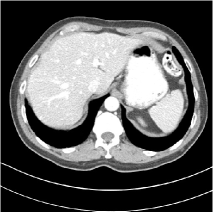

Refer to caption

Fig. 4: FBP images of test examples.